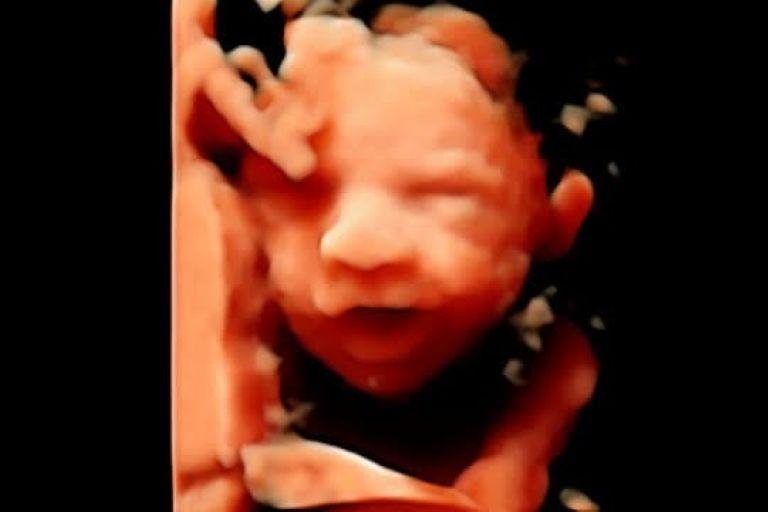

• Ultrassom Obstétrico

Acompanhamento completo da gestação com exames de alto e baixo risco, incluindo ultrassom obstétrico simples, com Doppler, Doppler com perfil biofísico fetal (PBF) e ultrassom morfológico do 1º, 2º e 3º trimestre.